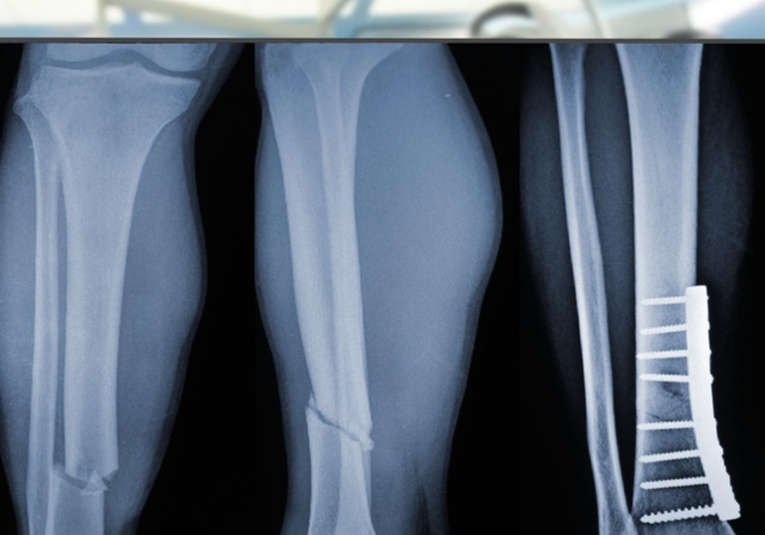

A diferencia de los métodos tradicionales, que requieren placas metálicas, clavos o tornillos, el Bone 02 utiliza una tecnología adhesiva inspirada en la naturaleza, particularmente en la capacidad de las ostras para adherirse de manera firme y estable a superficies húmedas y difíciles. Gracias a esto, la cirugía para reparar huesos se vuelve rápida, menos invasiva y con mejores resultados a largo plazo.

El pegamento se aplica mediante una sola inyección, a través de una pequeña incisión de entre 2 y 3 centímetros. Una vez introducido, el material actúa de inmediato fijando los fragmentos óseos en el lugar correcto. En cuestión de minutos, la sustancia se endurece, creando una unión resistente y duradera que permite que el hueso comience su proceso natural de cicatrización sin necesidad de implantes metálicos.

Según reportes oficiales, el pegamento posee una resistencia mecánica comparable a las placas de titanio, pero con la ventaja de que no requiere cirugías posteriores para retirar el material. Además, el adhesivo es biocompatible y se degrada de manera controlada a medida que el hueso recupera su integridad original.